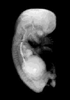

Carnegie Stage 23 (56 post-ovulatory days)

Most embryos at stage 23 are approximately 56-57 postovulatory days old and measure 23-32 mm in length. Distinguishing criteria for this stage include fusion of the eyelids at the medial and lateral margins, clear distinction of the subdivisions of the upper and lower limbs, the forearms appear at or above the level of the shoulders, the superficial vascular plexus of the head is very close to the vertex, and the external genitalia are well developed but not always sufficiently to distinguish the embryo's sex.

(NOTE: These specimens are late stage 23.)